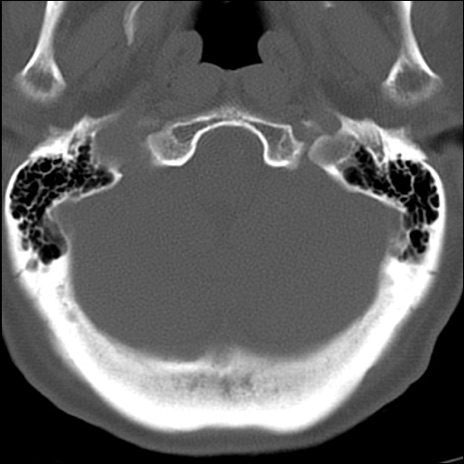

症例48 頚椎CT(横断像)

頚椎CT